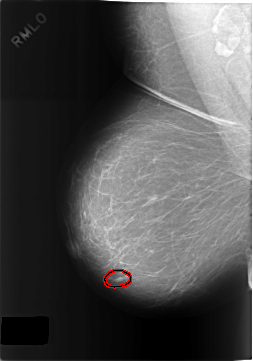

C_0317_1.RIGHT_MLO

FILE: C_0317_1.RIGHT_MLO.OVERLAY

TOTAL_ABNORMALITIES 1

ABNORMALITY 1

LESION_TYPE MASS SHAPE OVAL MARGINS MICROLOBULATED

ASSESSMENT 3

SUBTLETY 5

PATHOLOGY BENIGN

TOTAL_OUTLINES 1

BOUNDARY